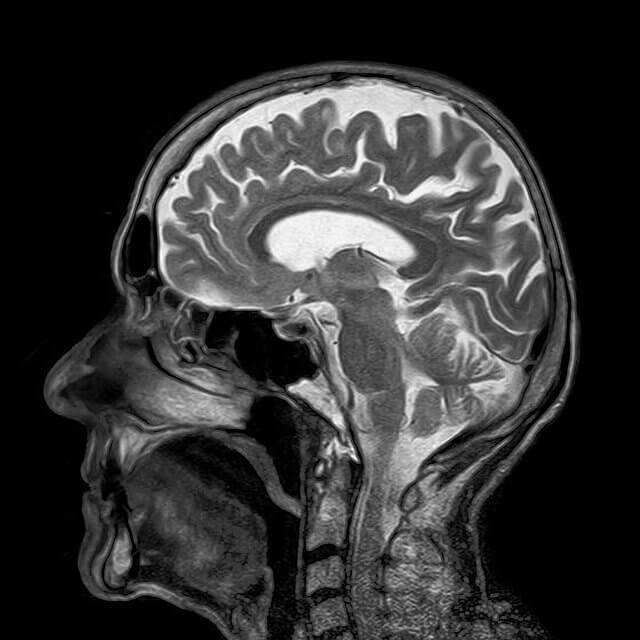

뇌졸중 초기증상, 자가진단 방법 골든타임을 놓치지 마라

뇌졸중은 우리나라 대한민국 사망원인 3위, 전 세계적으로는 두 번째로 높은 사망원인이다. 골든타임을 놓치면 대부분이 사망에 이르거나 심각한 후유장애를 남기는 중증 질환이다. 따라서 뇌졸중 초기증상이 나타났을 때 촌각을 다투면서 빨리 대응해야 한다.

뇌졸중의 원인을 알아보기 전에 "뇌졸중"이라는 용어의 뜻은 크게 두 가지로 나뉜다. 뇌혈관이 터지면서 발생하는 뇌출혈과 뇌혈관이 막히면서 발생하는 뇌경색이 있다.